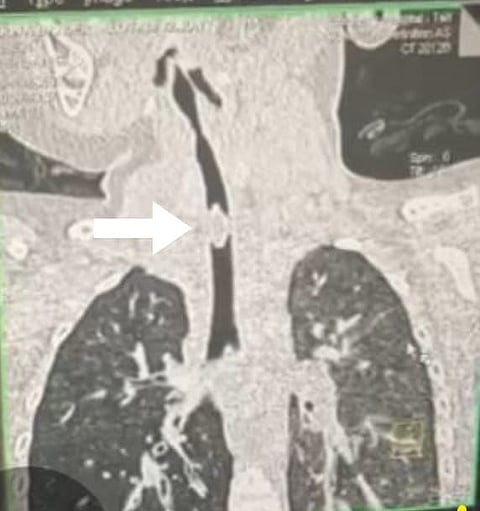

وقال المتحدث باسم صحة الطائف سراج الحميدان لـ"سبق": "بينت الأشعة المقطعية للطفل انسداداً شبه كامل ووجود جسم بمجرى التنفس الرئيسي بالقصبة الهوائية، وعلى الفور تم التدخل من خلال منظار شعبي صلب علاجي لإزالة الجسم الغريب (حبة فصفص)، وكان ذلك بالتنسيق الكامل مع أطباء التخدير لخطورة الحالة".